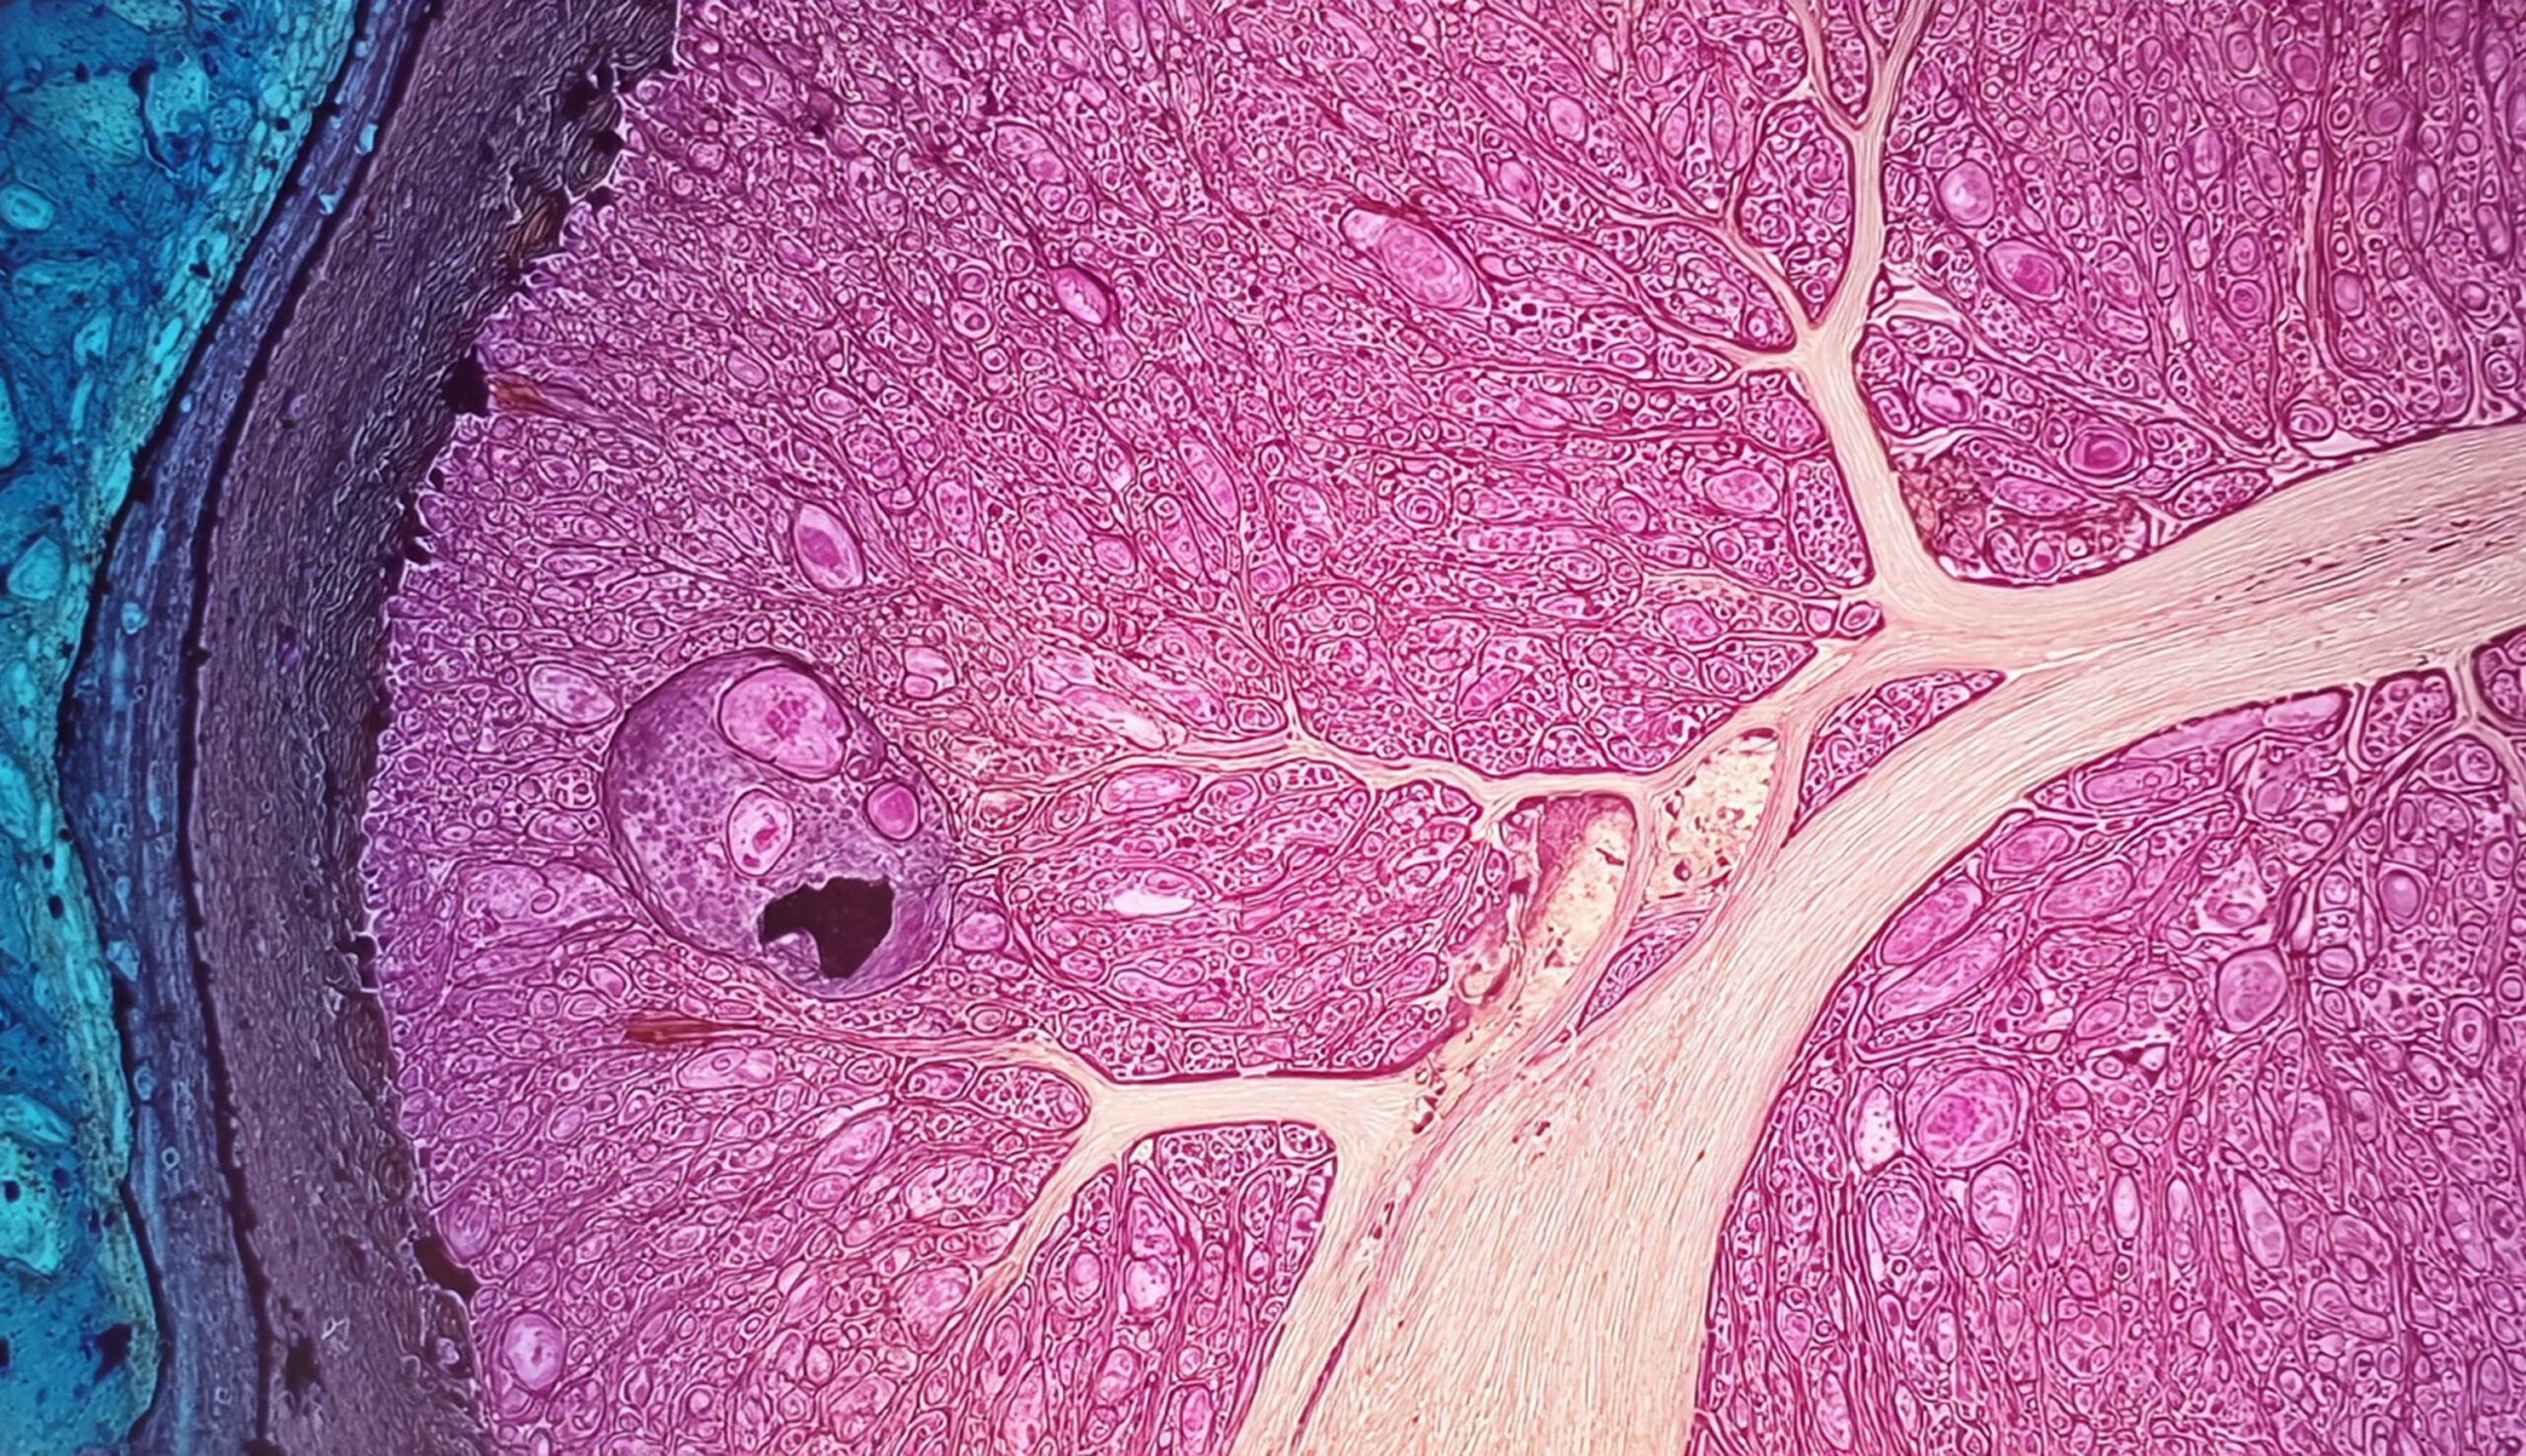

Microscopic image of a stained histological tissue section, likely a kidney

Microscopic image of a histological slide showing lymph node tissue